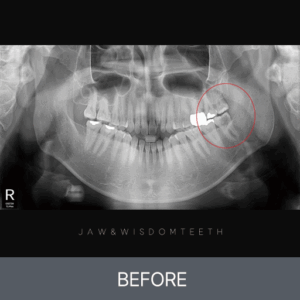

턱관절 CASE